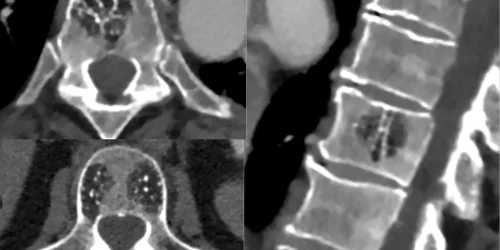

The most frequent primary tumor of the spine is a spinal hemangioma. These lesions are vascular in nature and frequently…